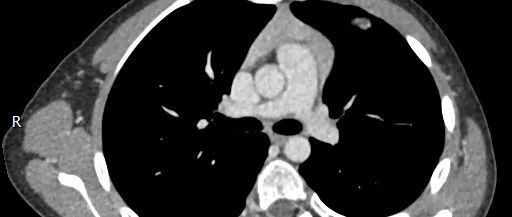

医学影像 yxyx-app 医学影像APP,打造伴随医生快速成长的影像学习社区。与影像园(Xctmr.com)一起提供最全面的影像案例库、基础(解剖、病理、影像诊断)知识、影像技术及考题等,为医生提供最佳的医学影像参考。【所属科室】呼吸科【基本资料】患者,女,20岁【主诉】干咳伴胸痛半月【影像图片】【讨论问题】如何诊断?【医学影像APP用户讨论】评论:左前纵隔见一囊样包块影,内见结节状、条片状脂性密度影,局部囊壁见壁结节影,增强见囊壁及壁结节明显均匀强化;上纵隔脂肪间隙密度增高,但与包块分界尚清,增强后内未见明显强化;肺动脉主干及左侧肺动脉见受压推移,未见充盈缺损影。前纵隔占位,考虑畸胎瘤。...